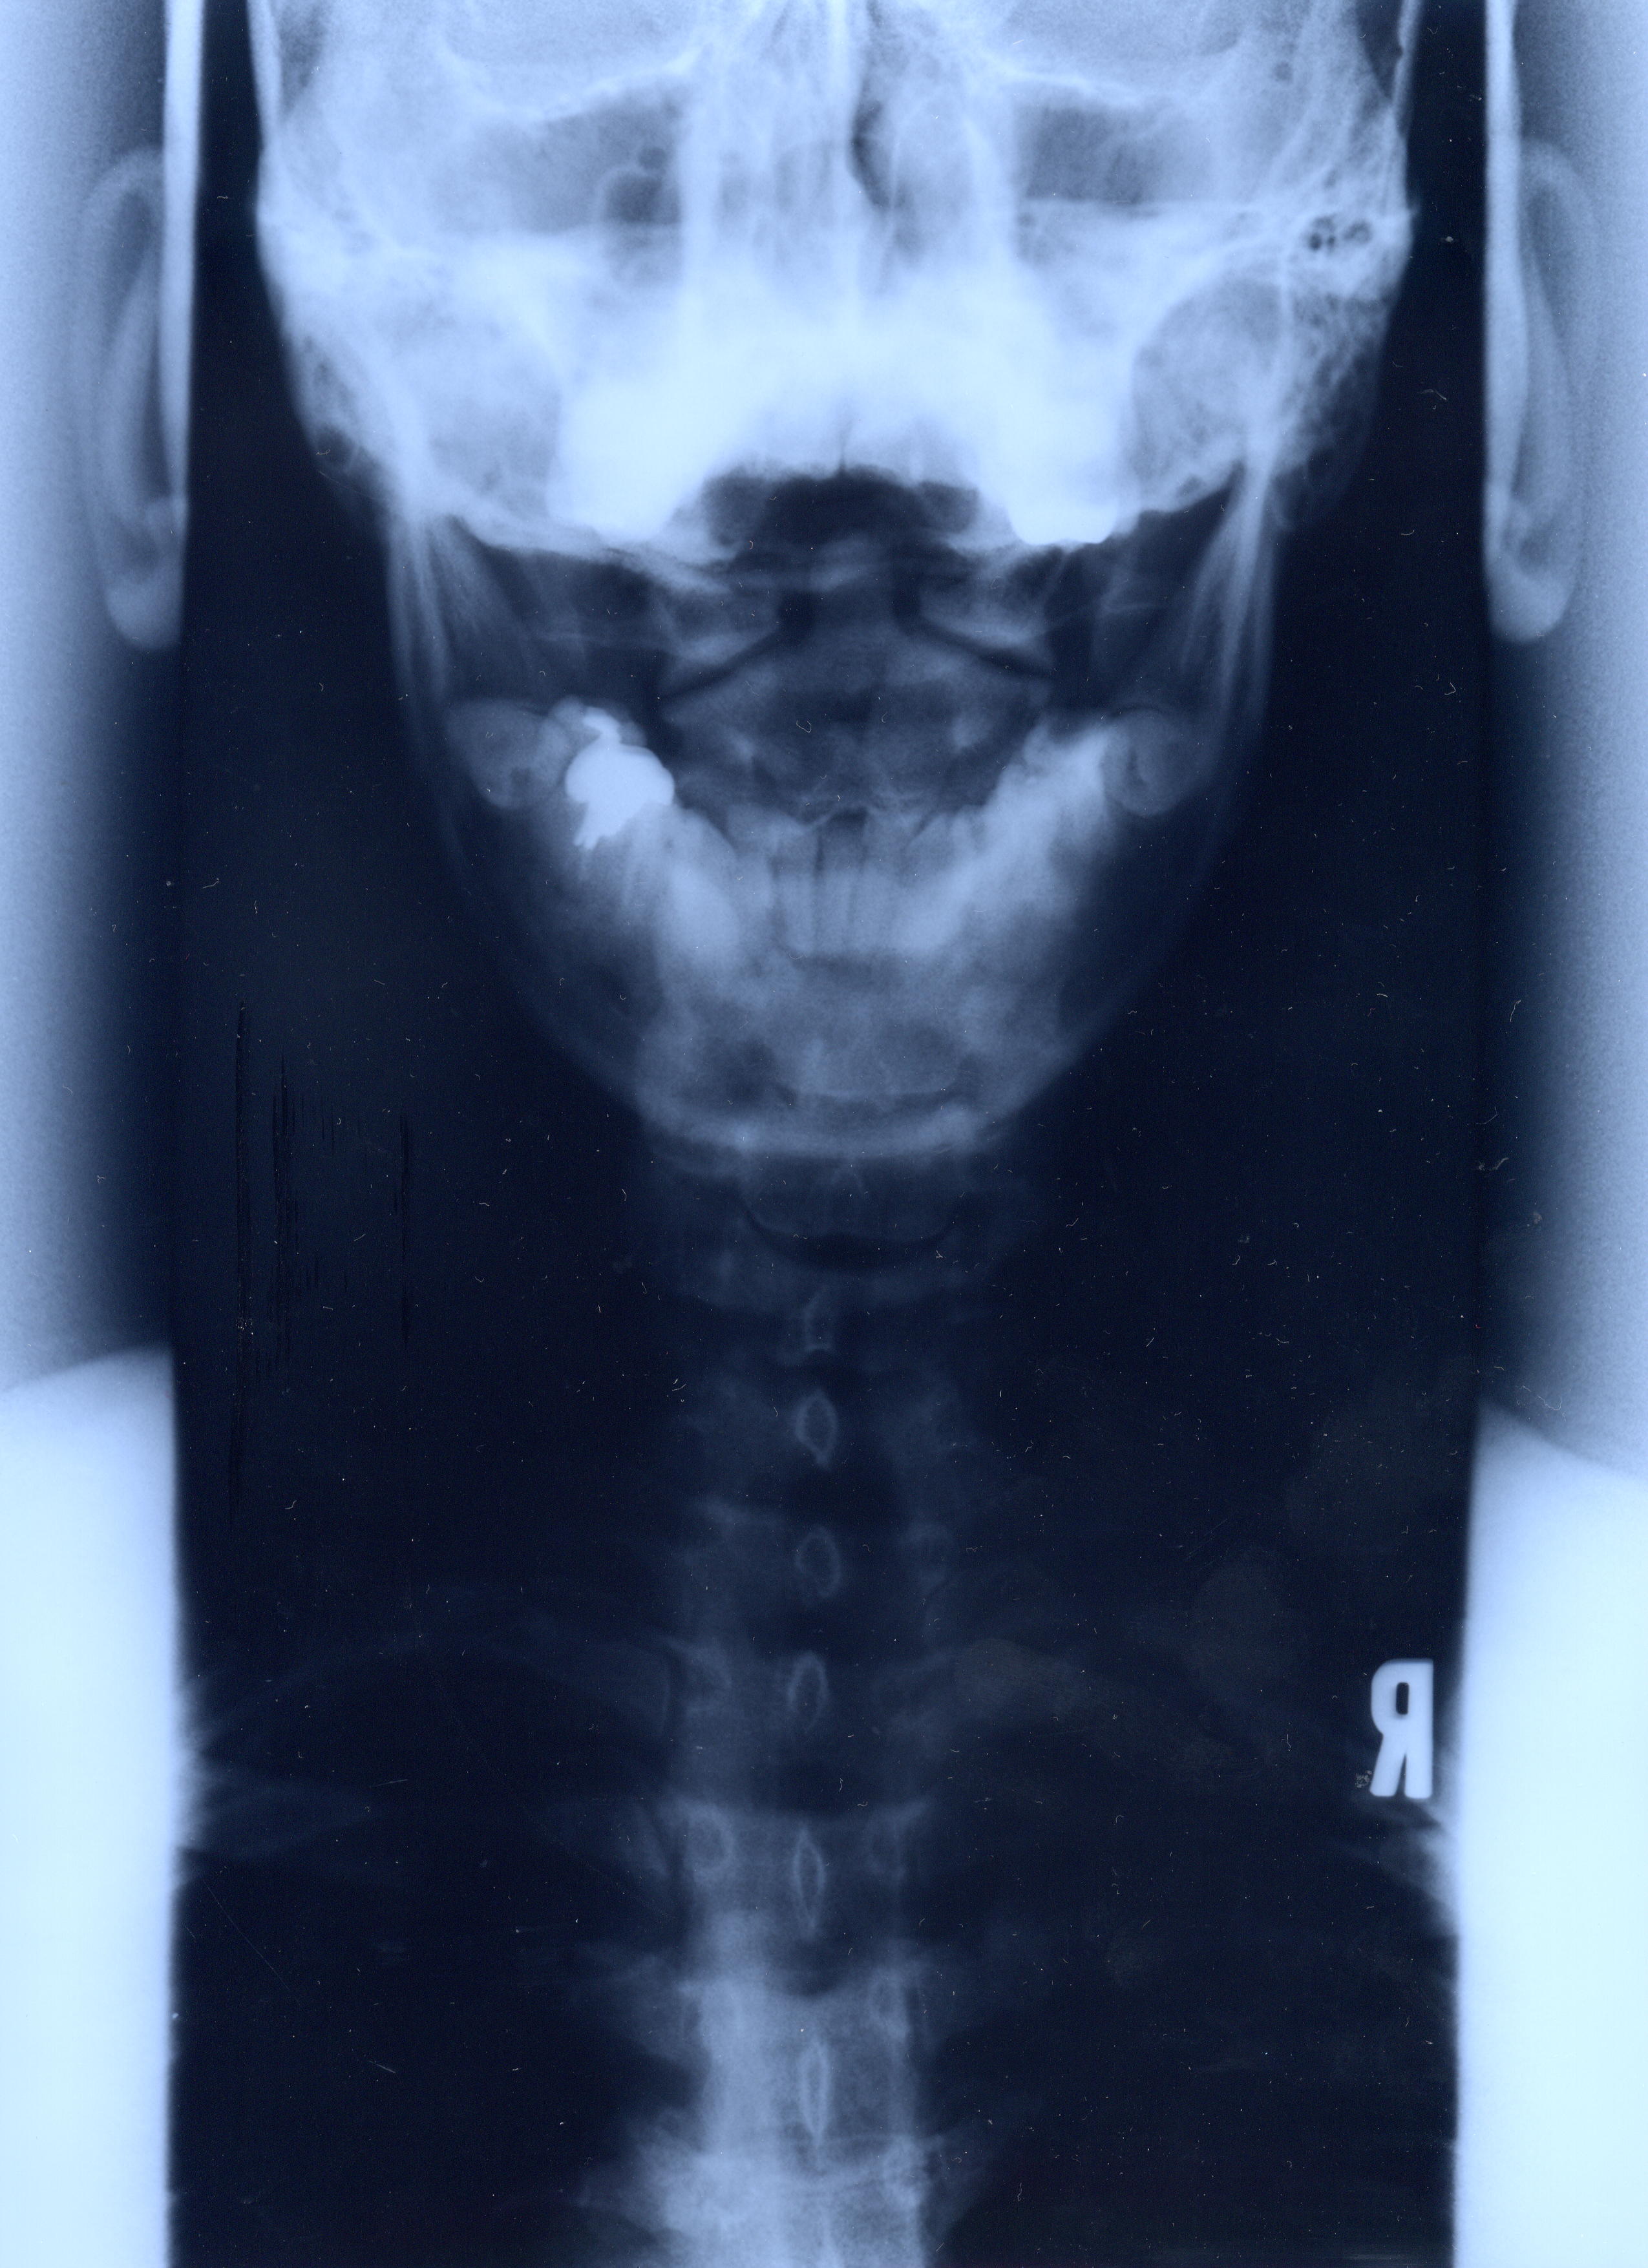

@@Ž„‚Μ”wœ‚Μ‚wόŽΚ^‚Ε‚·@@˜‚ͺ’Ι‚­‚Δ’Ι‚­‚āII@2002/1/22ŽB‰e

‚RDŽρ‚Μ‰‘}@Šg‘ε